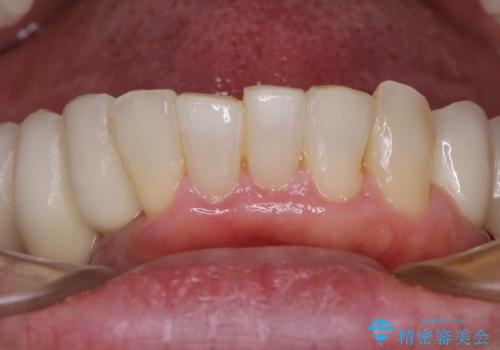

歯を抜かないといけない部分はインプラントとオールセラミッククラウンにより咬合を回復させ、歯周外科処置を行う歯については、同じくオールセラミッククラウンにて補綴治療を行うこととしました。

外科処置を多く行ったため、その待ち時間が長くかかり、さらには途中矯正治療も行なったので、治療期間は長期間となりました。

痛みには強い方であったため、治療はそれほど苦痛とは感じられず、毎回楽しく通院してくださいました。